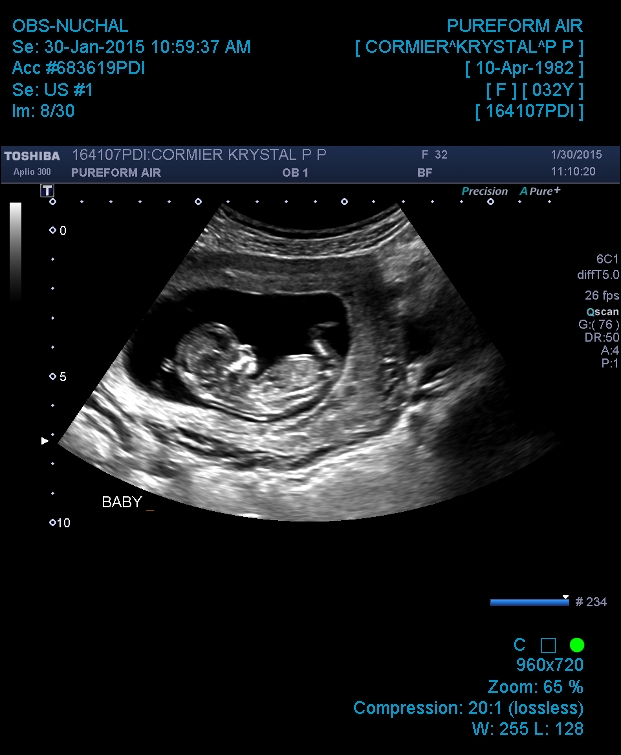

Attachment 23474Attachment 23475

cute baby :) can't really tell as cant see the end of the nub and baby is at a slight angle but a lovely profile shot, congratulations xx